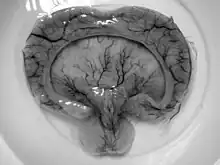

| Gross pathology specimen from a case of alobar holoprosencephaly, a clinical manifestation of Young–Madders syndrome first described as a new condition by doctors Young and Madders in 1987. |

Young–Madders syndrome, alternatively known as Pseudotrisomy 13 syndrome or holoprosencephaly–polydactyly syndrome, is a genetic disorder resulting from defective and duplicated chromosomes which result in holoprosencephaly, polydactyly, facial malformations and intellectual disability, with a significant variance in the severity of symptoms being seen across known cases.[1] Many cases often suffer with several other genetic disorders, and some have presented with hypoplasia, cleft lip, cardiac lesions and other heart defects. In one case in 1991 and another in 2000 the condition was found in siblings who were the product of incest. Many cases are diagnosed prenatally and often in siblings.[1] Cases are almost fatal in the prenatal stage with babies being stillborn.

Young–Madders syndrome is detectable from the fetal stage of development largely due to the distinctive consequences of holoprosencephaly, a spectrum of defects or malformations of the brain and face. Facial defects which may manifest in the eyes, nose, and upper lip, featuring cyclopia, anosmia, or in the growth of only a single central incisor, and severe overlapping of the bones of the skull.[2][3] Cardiac and in some cases pulmonary deformities are present.[2] Another signature deformity is bilateral polydactyly, and many patients also suffer from hypoplasia and genital deformities.[1]